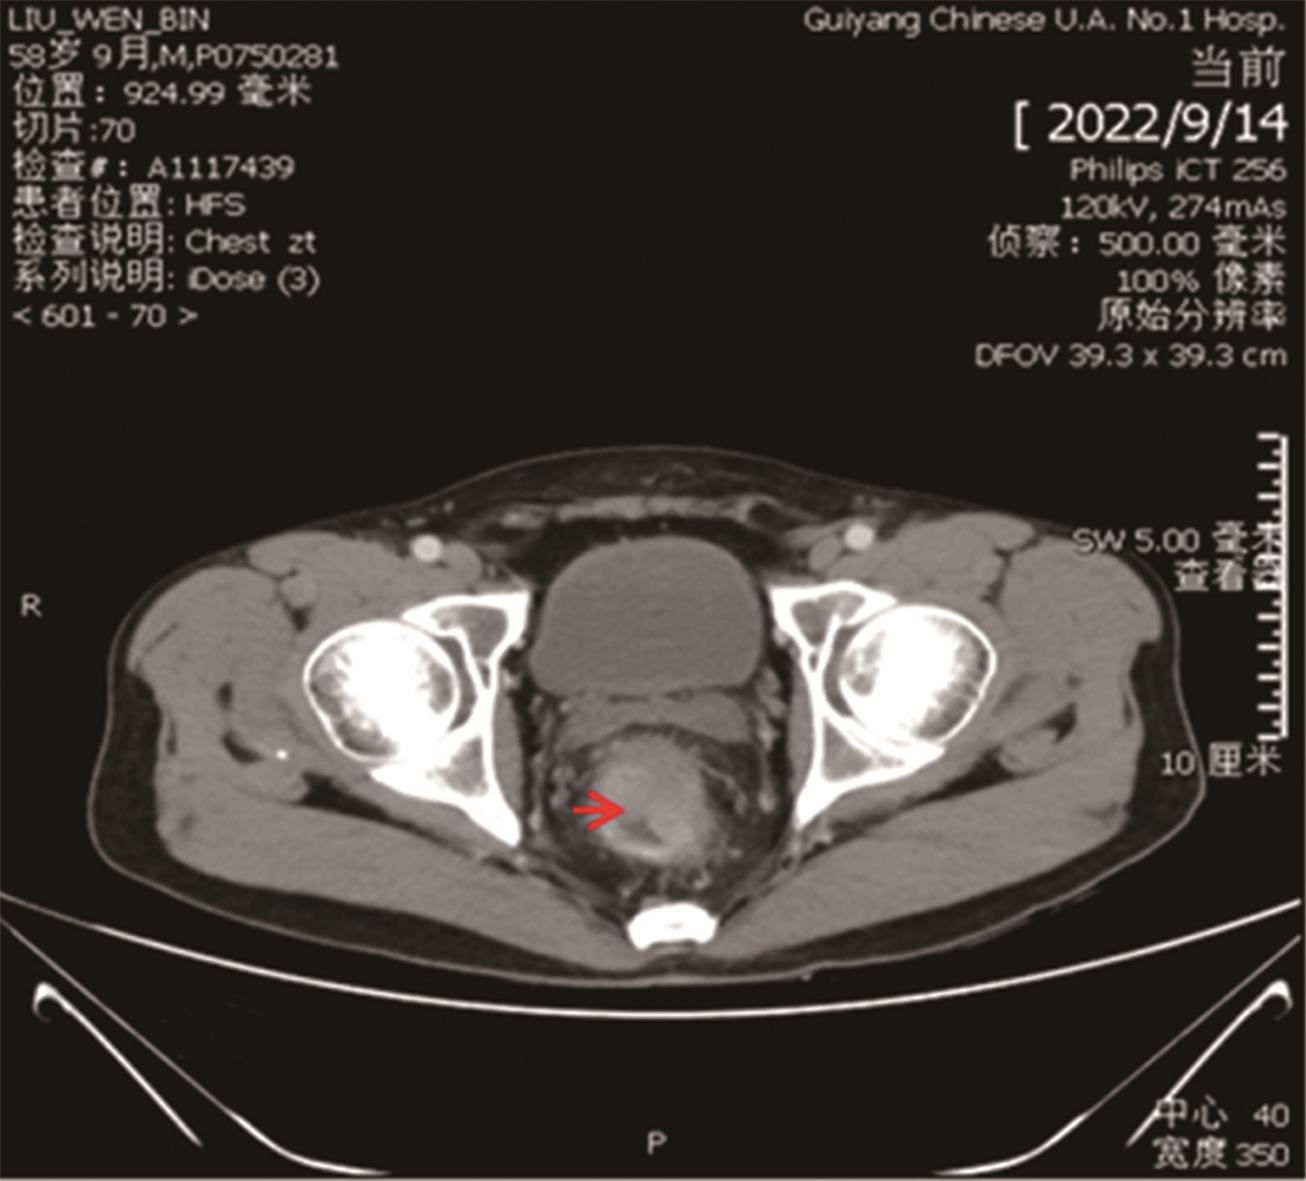

• “镜面人”保留左结肠动脉腹腔镜低位直肠癌根治术1例

2023, 48(7):853-856. DOI: 10.13406/j.cnki.cyxb.003278

摘要 (87) HTML (56) PDF 3.64 M (283) 评论 (0) 收藏